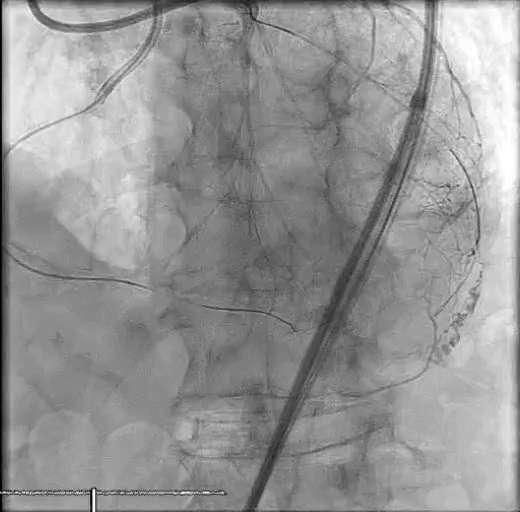

A woman in her late 60s with a history of coronary artery disease presented for proximal left anterior descending PCI in the setting of a non-ST-elevation myocardial infarction (Figure 1A). The procedure was complicated by a distal coronary artery perforation caused by a coronary wire (Figure 1B, Video 1). The patient remained hemodynamically stable.

Figure 1. Initial angiography with severe stenosis of the proximal left anterior descending (blue arrow) (A). After intervention, a coronary artery perforation is seen in the distal vessel (blue arrow) (B). Transthoracic echocardiography showing the left ventricle and right ventricle (C). CEE after intracoronary injection of the UEA, the UEA is seen filling the right ventricle while notably absent from the pericardium (D).

After balloon tamponade, continued extravasation was present on angiography. CEE was performed with an intracoronary injection of an UEA. The UEA was seen filling the cardiac chambers, but no pericardial effusion was seen and there was no UEA identified filling the pericardial space (Figures 1C and 1D, Video 2). Together with the angiographic finding, we determined the perforation was likely into a coronary vein. No further intervention was performed. The patient remained hemodynamically stable and was later discharged without significant events.